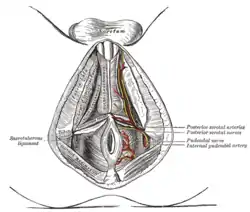

The superficial branches of the internal pudendal artery. The posterior aspect of the rectum exposed by removing the lower part of the sacrum and the coccyx.

The posterior aspect of the rectum exposed by removing the lower part of the sacrum and the coccyx.